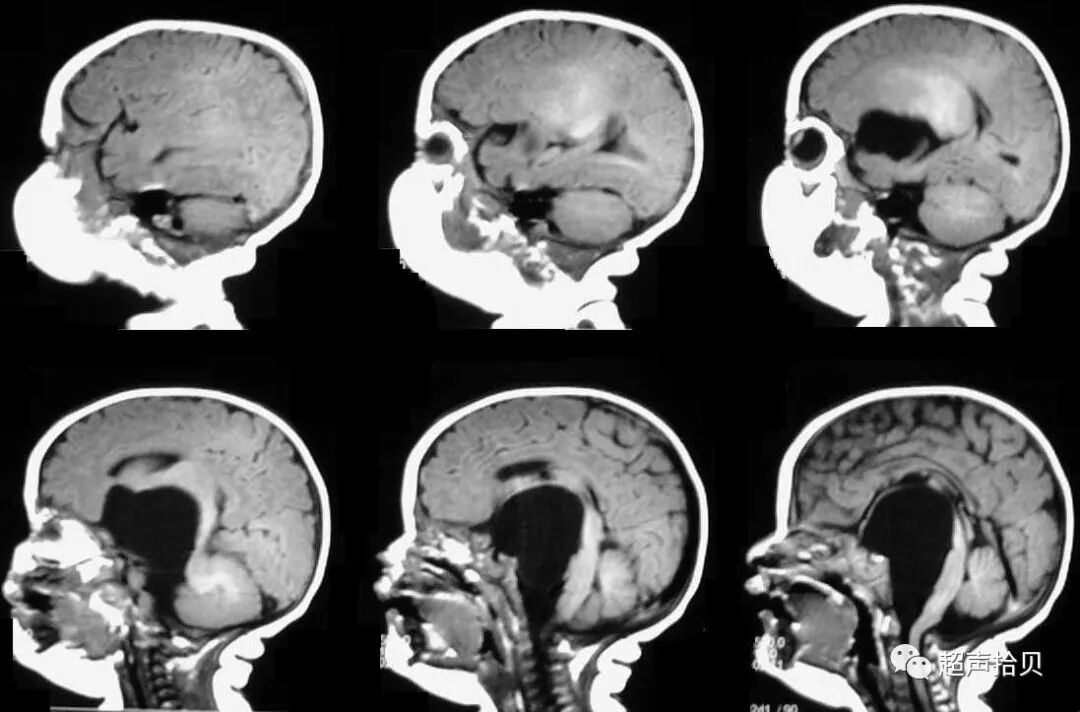

图像8,9:MRI; 怀孕32周; 通过胎儿颅骨的横切面显示扩张的侧脑室和主要的半球间囊肿向右延伸。

图像10,11:MRI; 怀孕32周; 横向(图像11,左侧)和旁矢状切面(图像12,右侧)穿过胎儿颅骨显示扩张的侧脑室和半球囊肿。

一周后,进行第二次扫描以评估进展性结果。 囊状结构和侧脑室分别扩大到28×25毫米和13毫米大小。 矢状位图显示脑干向后位移,阻塞脑室循环(图2,A和B)。 胼胝体正常发育,血流正常,无颅内压增高(图2C)。 三维超声显示孤立的圆形囊状结构(图3)。 使用产前超声检查结果进行胎儿MRI并确认鞍上位置(图4)。 怀疑是蛛网膜囊肿,囊肿和蛛网膜下腔之间可能存在解剖联系的球阀机制被认为是囊肿扩大的原因;

图4:妊娠26周时的产前MRI:第三脑室蛛网膜囊肿的横向(A),矢状(B)和冠状面(C)平面引起脑室扩张

图5:出生后1周进行T1加权轴位MRI扫描。 侧脑室的后角和前角,特别是第三脑室,被蛛网膜囊肿占据。